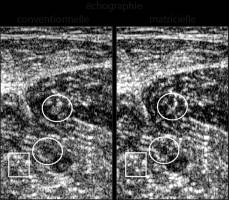

En échographie conventionnelle, les variations de la structure des tissus mous induisent une distorsion des fronts d'onde ultrasonore. Elles floutent l'image et peuvent donc nuire au diagnostic médical. Aussi, des chercheurs et chercheuses de l'Institut Langevin (CNRS/ESPCI Paris-PSL) 1 ont mis au point une nouvelle méthode d'imagerie échographique non invasive surmontant ces phénomènes d'aberrations.